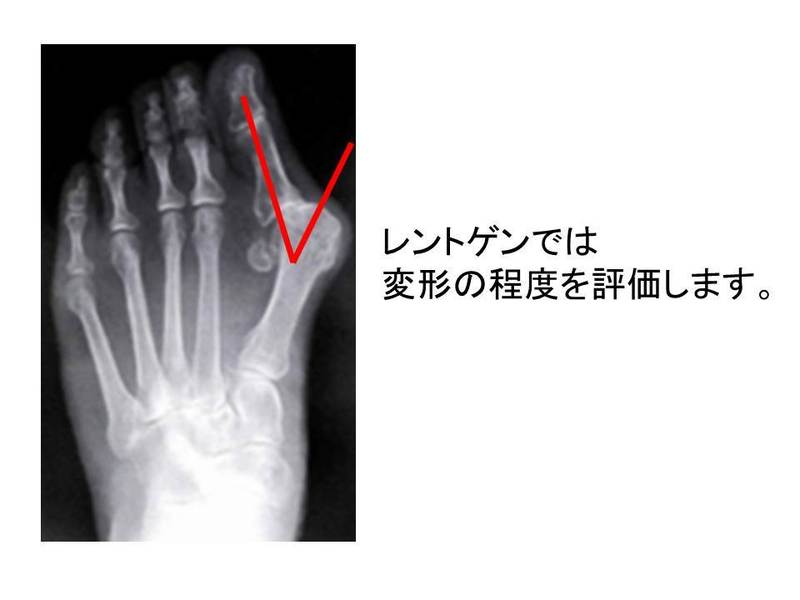

⑤ 画像所見

レントゲンでは、変形の程度を評価します。